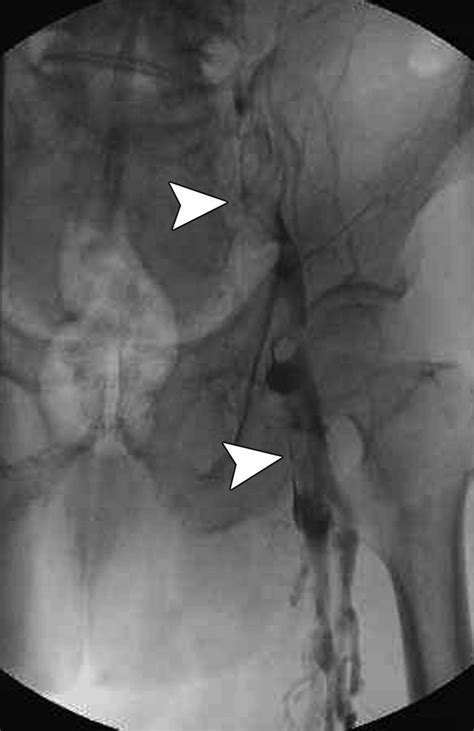

• Angioplasty: A procedure where a balloon is inserted into the vein to widen it and relieve compression.

• Stent placement: A small mesh tube is placed in the vein to keep it open and prevent further compression.